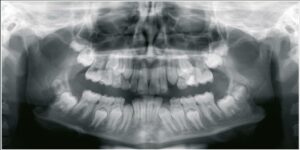

Panoramic X-Ray Machines: Applications, Types & Cost

Over the past two decades, dental imaging has advanced and altered in both numerous and impressive ways. Prior to today, dental professionals had to circumnavigate the issue that there were only a few panoramic film X-ray brands to choose from when purchasing a panoramic X-ray machine for their business. Another common problem was that the […]